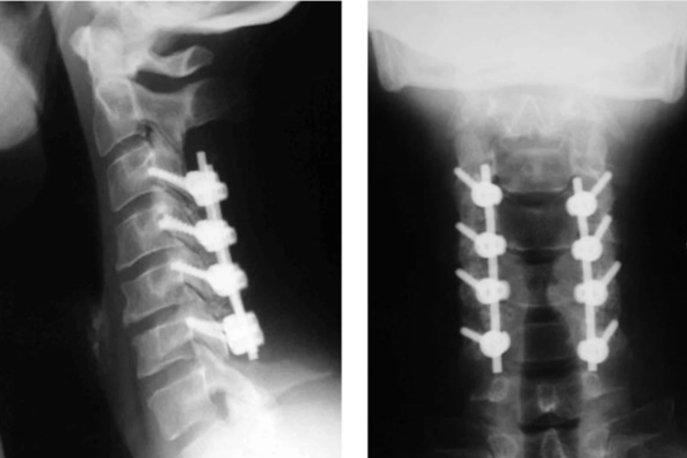

ACDF (Fusion)

Anterior Cervical Discectomy and Fusion to remove a damaged disc and fuse vertebrae.

Anterior Approach

Procedure typically performed through the front of the neck for better access.